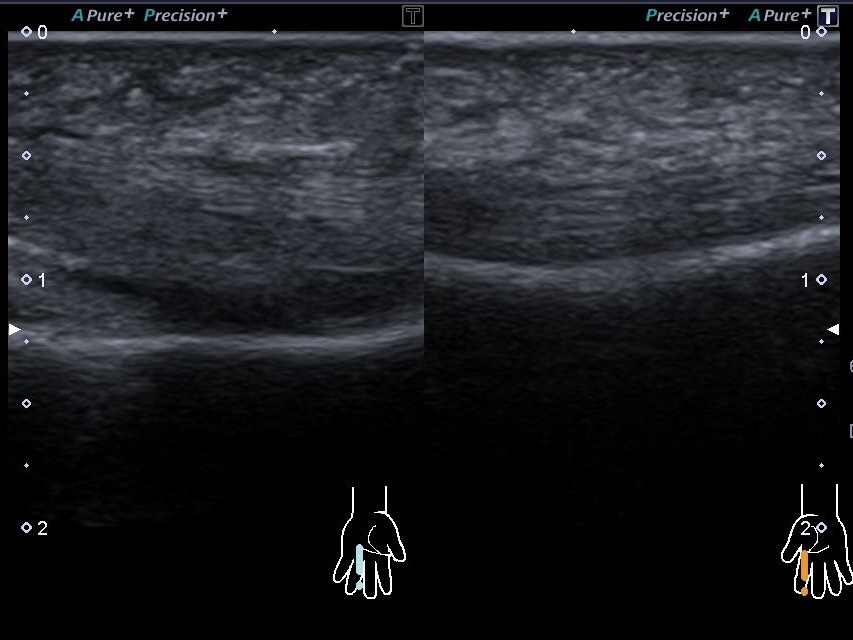

В ходе ультразвукового исследования было обнаружено:

1. Выраженное воспаление подкожной жировой клетчатки.

2. Синовит межфалангового сустава.

3. Теносиновит (воспаление сухожилия) сгибателя пальца.

4. Точная локализация шипа в месте прокола.

При диагнозе Plant thorn synovitis решение проблемы возможно только хирургическим путем. Благодаря УЗИ врач-диагност сделал точную разметку места залегания инородного тела для хирургов.